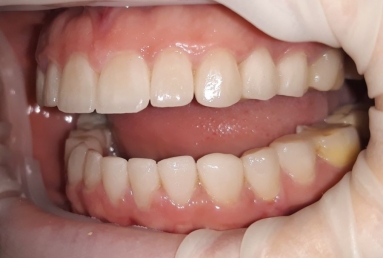

orthodontic treatment, full ceramic crowns

Our patient had general dental abrasion due to maloclusion. After orthodontic treatment, the upper teeth received full ceramic crowns, while the lower were restored with crowns and veneers.

We managed to solve partialy the orthodontic problem and at the same time restore the frontal teeth with esthetic ceramics for a perfect smile.